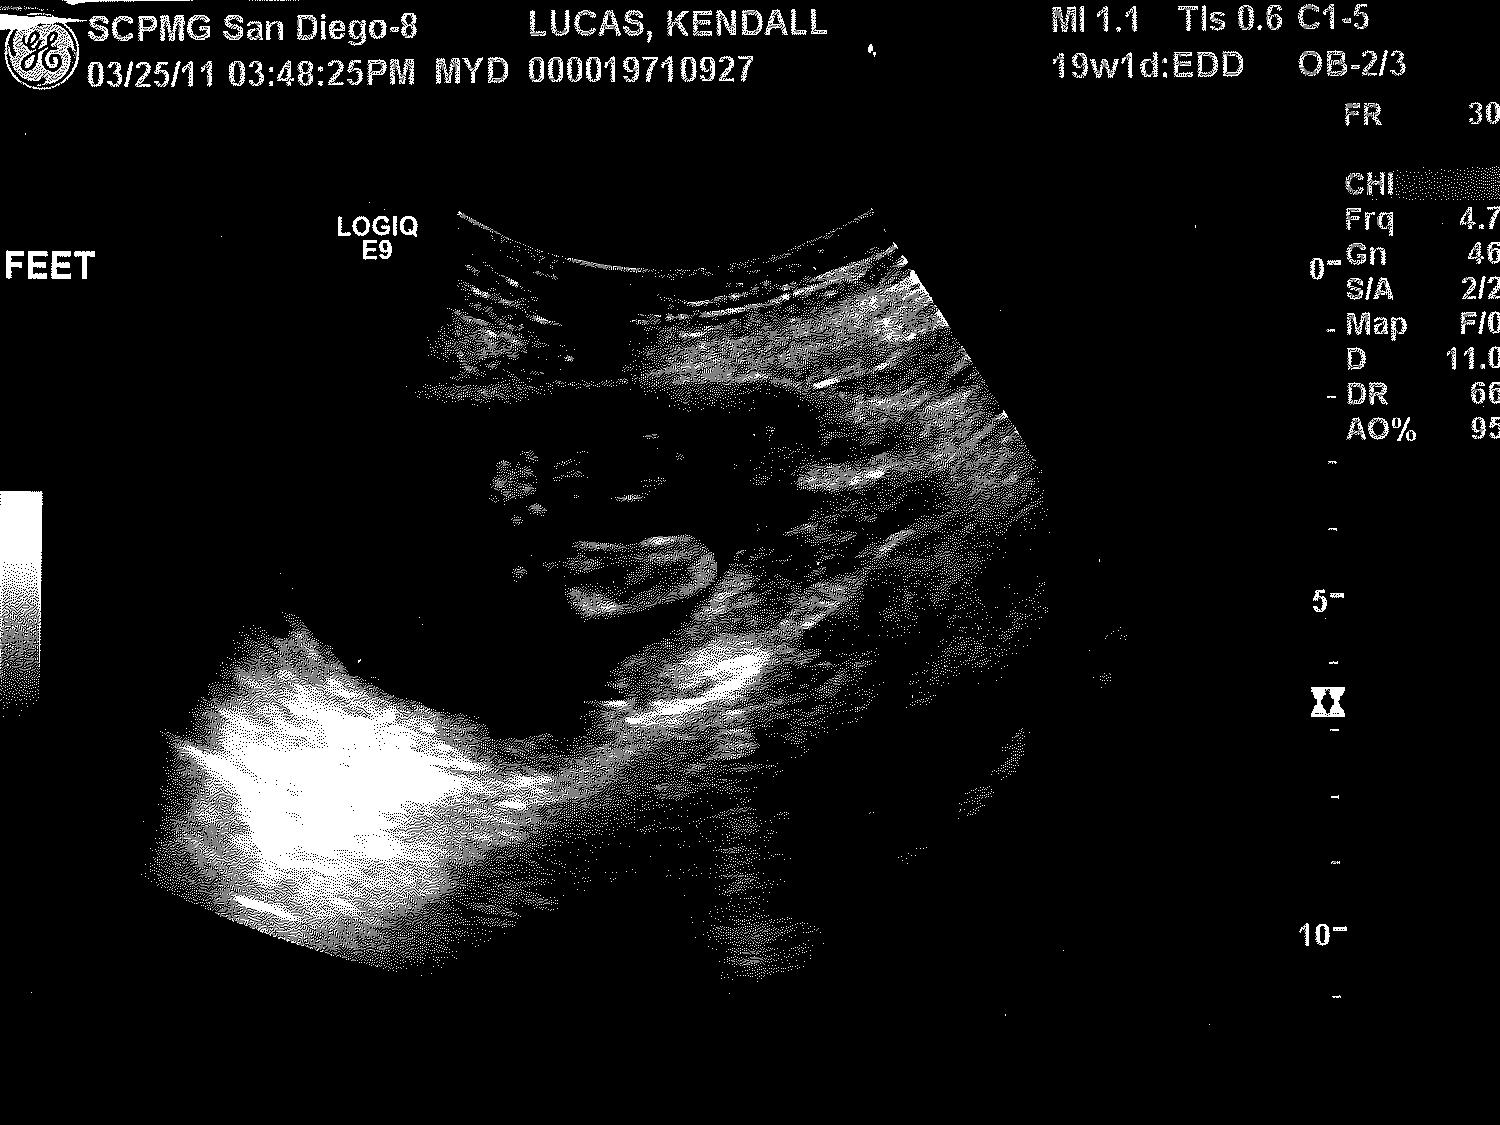

OK! Now to the stuff you have probably been waiting for...ULTRASOUND PICTURES!!! We had a great time at our ultrasound appointment and had a great technician who took lots of wonderful pictures for us. Enjoy.

| Baby's Feet |